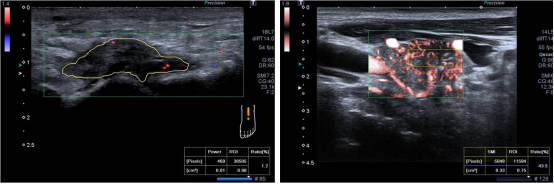

2. 高级动态血流成像技术ADF:该技术是佳能独创的彩色多普勒成像技术,具有高分辨率、高敏感、高帧频的血流成像特点,可以高分辨显示微细血流信息。

3. i系列超微血流成像技术iSMI:i系列的SMI称为iSMI,结合Aplio i系列创新的平台技术,成像能力得到进一步提升,实现更加敏感、更高分辨率、更少伪像的极低速血流显示。iSMI技术是彩色多普勒技新性的突破,具有广泛的妇产临床应用价值:子宫内膜疾病,妇科良恶性肿瘤的诊断和鉴别诊断以及术前术后评估,瘢痕妊娠,胎盘植入,最早显示胎儿先心病的异常血流,胎儿肾脏血流,肺脏血流灌注等。

iSMI两种模式:

1彩色模式(cSMI):同时显示组织的二维灰阶信息和彩色血流信息,

2减影模式(mSMI):抑制组织的二维灰阶信息,利用灰度信号来凸显血流信息。